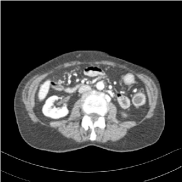

Refer to caption FBPRMSE = 194.09 HURefer to caption FBPRMSE = 194.09 HURefer to caption PWLS-ULTRARMSE = 43.40 HURefer to caption PWLS-ULTRARMSE = 43.40 HU

Refer to caption FBPConvNetRMSE = 34.24 HURefer to caption FBPConvNetRMSE = 34.24 HURefer to caption SUPER-FCN-DataTermRMSE = 31.21 HURefer to caption SUPER-FCN-DataTermRMSE = 31.21 HU

Refer to caption SUPER-FCN-ULTRARMSE = 28.82 HURefer to caption SUPER-FCN-ULTRARMSE = 28.82 HURefer to caption ReferenceRefer to caption Reference

Figure 5: Reconstructed images of slice 150 of patient L192 using of FBP, PWLS-ULTRA, FBPConvNet, SUPER-FCN-DataTerm, and SUPER-FCN-ULTRA, respectively, shown along with the reference.

Fig. 5 shows reconstructions using FBPConvNet, SUPER-FCN-DataTerm (i.e., β=μ=0𝛽𝜇0\beta=\mu=0), PWLS-ULTRA, and SUPER-FCN-ULTRA, respectively. For SUPER-FCN-DataTerm, when optimizing the data-fidelity term, we start with the deep network’s output and ran 5 iterations for the data-fidelity term to avoid overfitting to the analytical FBP images. In Fig. 5, obviously, FBPConvNet significantly suppresses noise and artifacts compared to PWLS-ULTRA, but it also over-smooths many details (e.g., features in the zoom-in box) in the reconstruction. SUPER-FCN-DataTerm, by enforcing data consistency, helps reduce overfitting issues and reconstructs image details and tissue boundaries better compared to the standalone FBPConvNet. Our SUPER-FCN-ULTRA method, however, exploits richer prior information (via the union of learned sparsifying transforms) and explicit network regularizer and outperforms the SUPER-FCN-DataTerm approach. Additional such comparisons for other selected test slices are included in the supplement (Fig. 15).